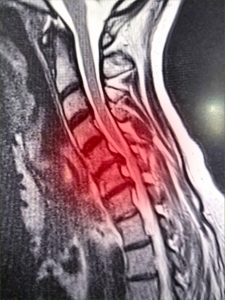

At Buxton & Bakewell Osteopathy Clinic we offer IDD Therapy, an advanced, non-invasive form of spinal decompression that bridges the gap between manual therapy and surgery. An example can be seen below of a trapped nerve in the neck before and after IDD Treatment using MRI